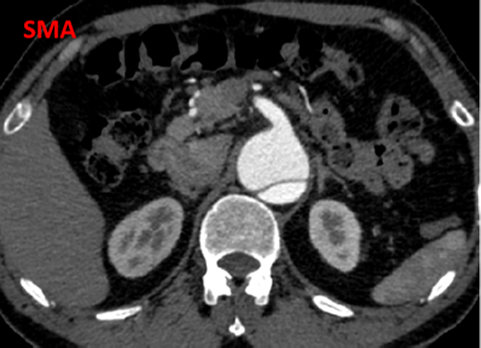

夹层近端封闭良好。夹层动脉瘤累及整个内脏区动脉,腹腔干、肠系膜上动脉假腔供血,腹腔干开口重度狭窄;右肾动脉真假腔供血,以假腔为主;左肾动脉真腔供血。肾下腹主动脉段无裂口,右侧髂外动脉存在裂口。

CT影像